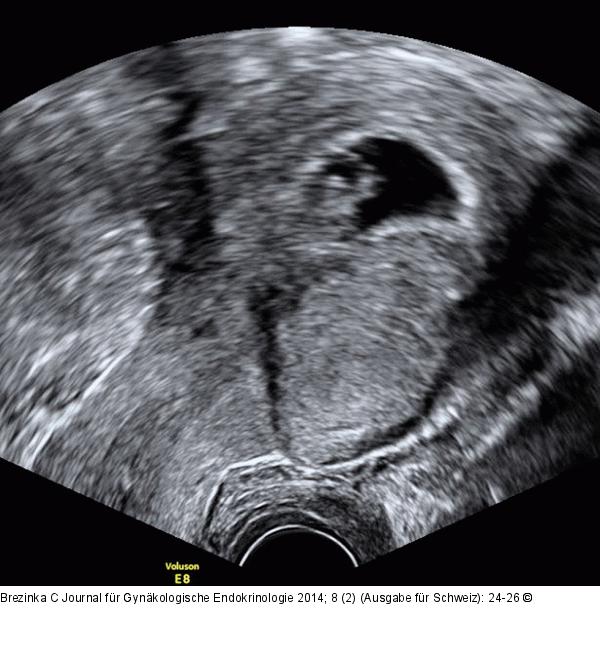

Abbildung 7: Gyn-Ultraschall Kurze Distanz zwischen Sectionarbe und Fruchtsack. |

Kurze Distanz zwischen Sectionarbe und Fruchtsack. |